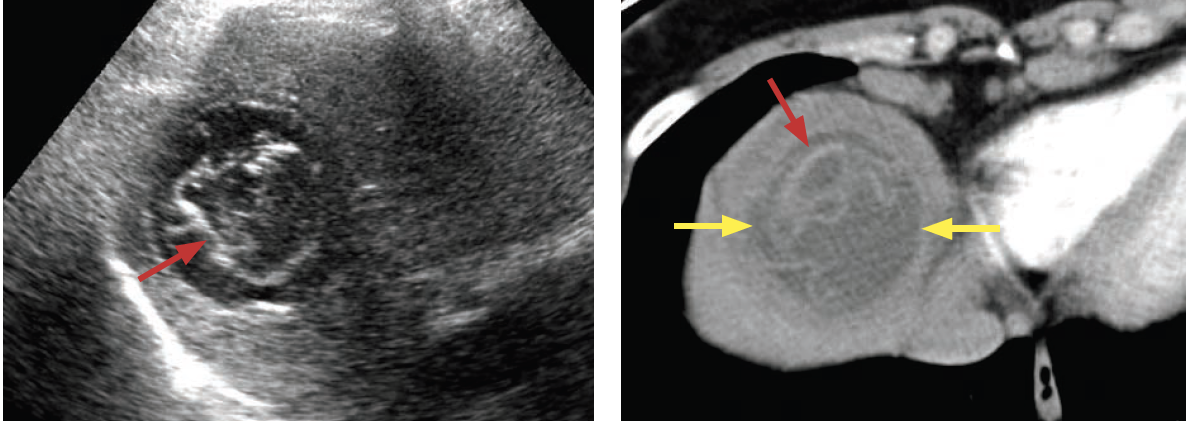

Diagnosis?

Echinoccal disease

Hepatic echinococcosis is caused by ingestion of the eggs of echinoccus granulosus (edemic in Mediteranean basin) with sheep herding

Echinoccal eggs develop into hydatid cysts which on CT loo like a well-defined hypoattenuating mass with a floating membrane or daughter cyst. Peripheral calcifications are possible